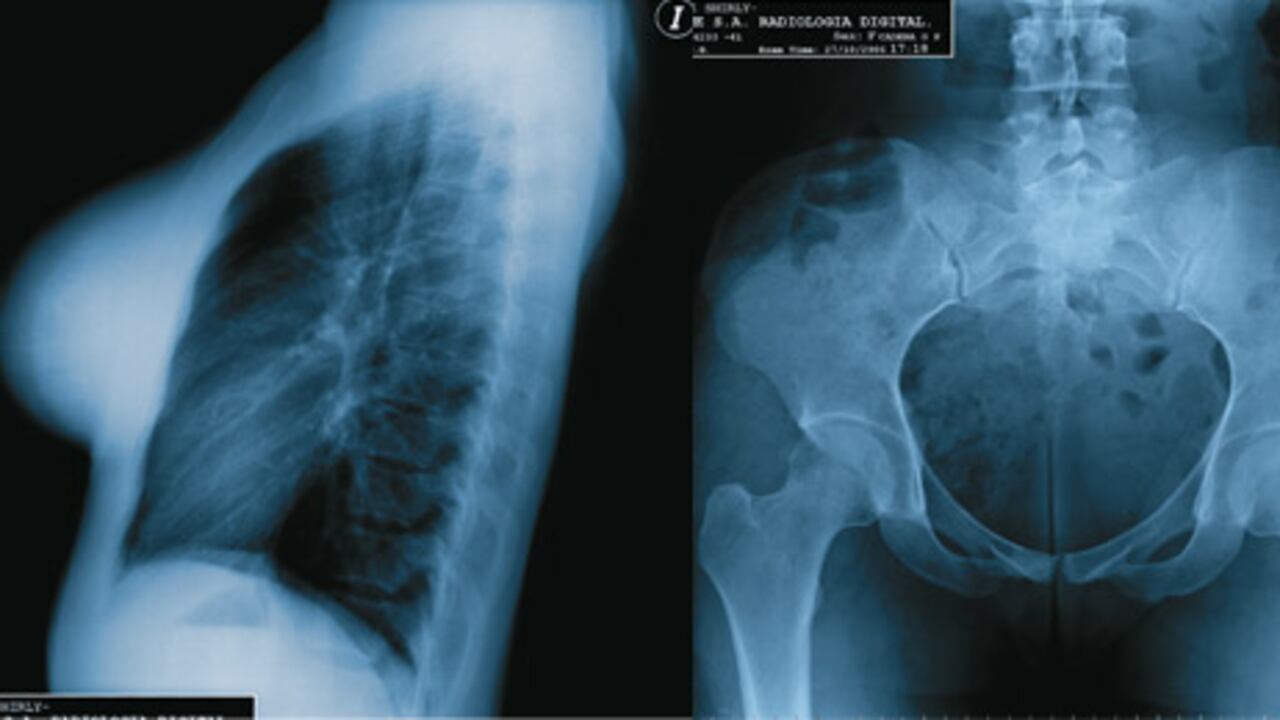

La radiografía muestra con claridad que hay prótesis en los senos. La imagen del tórax refleja normalidad. Sus campos pulmonares no tienen ninguna lesión, su expansión y transparencia son adecuadas. Todas las vías aéreas de su tráquea y bronquios no sufren alteraciones. La zona de la pelvis tiene una densidad ósea adecuada y no se ven lesiones o calcificaciones patológicas.